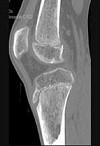

男,46岁,膝关节疼痛,结合图像,最可能的诊断是()A.骨质硬化B.骨质疏松C.骨质软化D.骨髓瘤E.转移瘤

问题 男,46岁,膝关节疼痛,结合图像,最可能的诊断是()

选项 A.骨质硬化 B.骨质疏松 C.骨质软化 D.骨髓瘤 E.转移瘤

答案 B